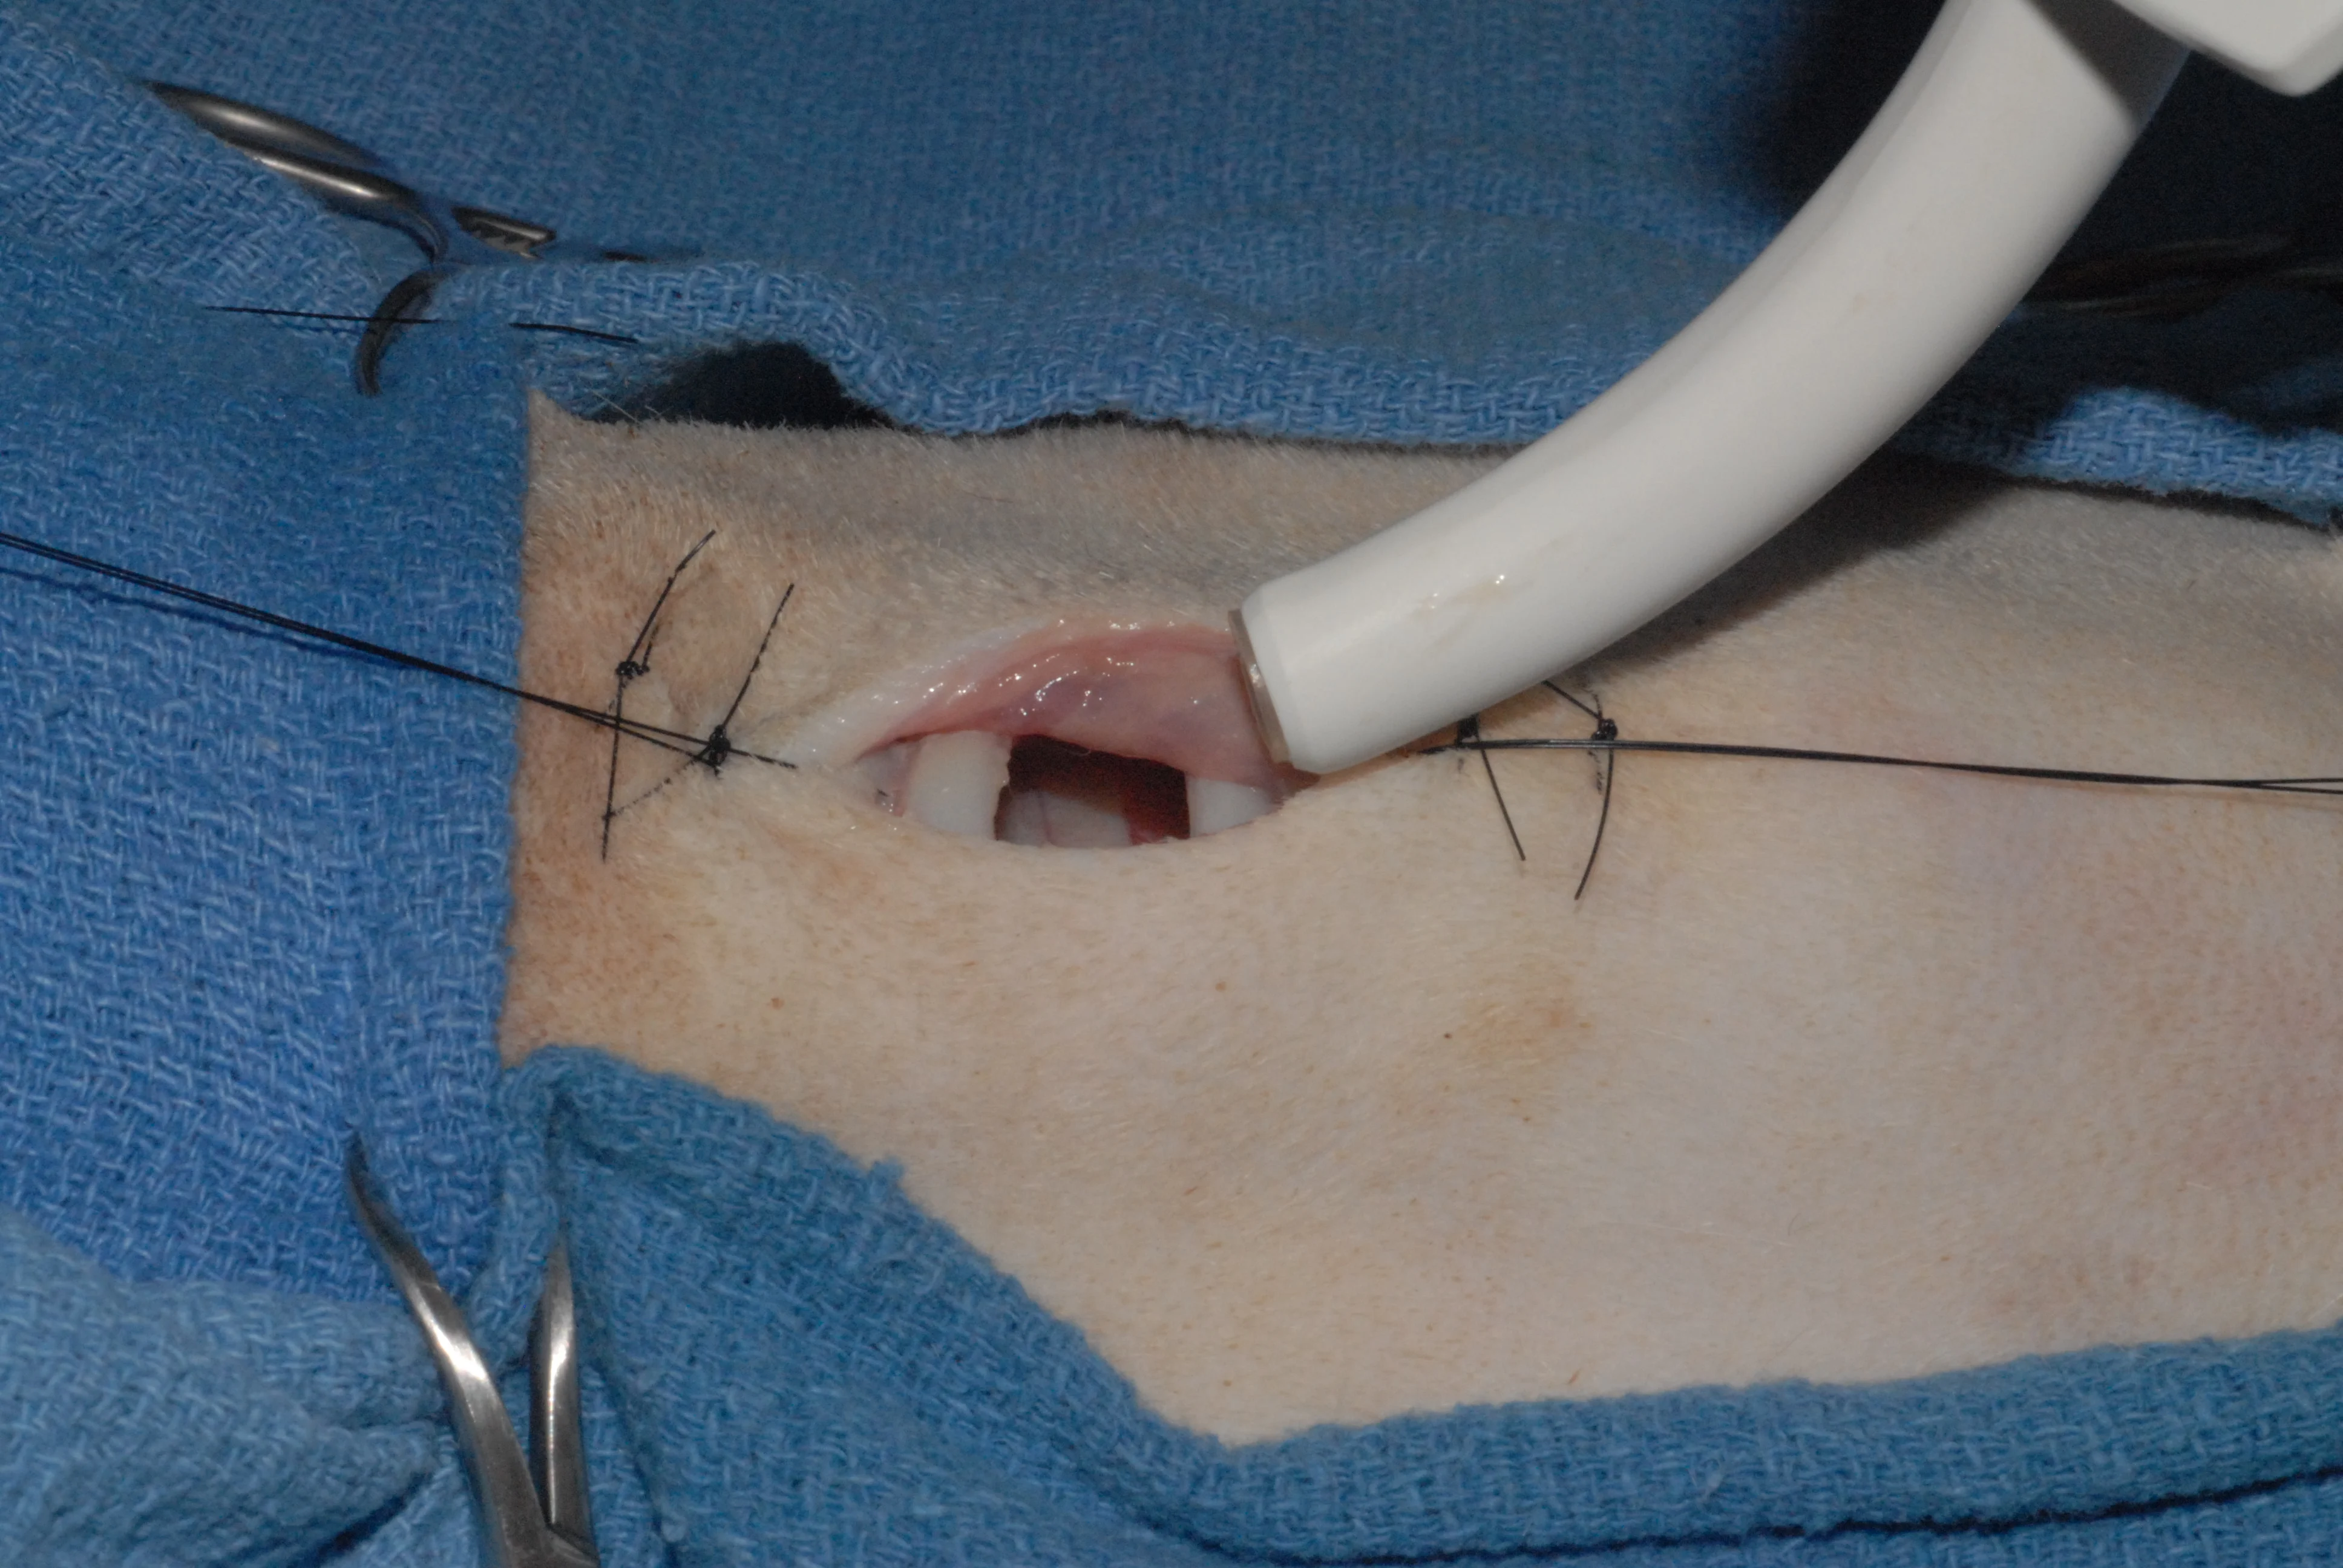

Step 9

With the tracheal incision made, the endotracheal tube is withdrawn (A) and the tracheostomy tube is inserted. Traction on the stay sutures will open the tracheal stoma for easy insertion of the tracheostomy tube (B).

A

Step 10

The tracheostomy site can be partially closed with a few subcutaneous and skin sutures. This decreases the size of the open wound. The tracheostomy tube should fill 50% to 60% of the tracheal lumen. A nonadherent pad is cut to go around the tracheostomy tube, and the neck is lightly bandaged. The bandage should be secure and not excessively bulky, since a large or shifting bandage could obstruct the tracheostomy tube. The tube is secured around the neck with umbilical tape or gauze to prevent dislodgement.